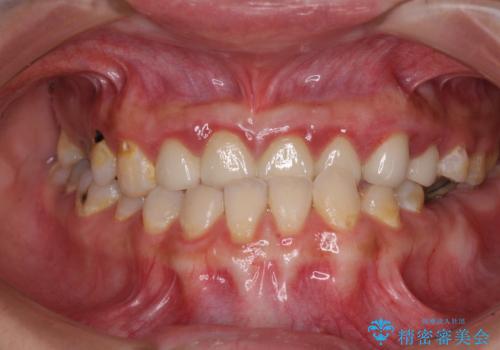

むし歯だらけの奥歯 セラミッククラウンによるむし歯治療

- 奥歯のむし歯を気にして来院された患者様です。

自身の口腔内への意識が高くなく、汚れが非常に多い方でした。

再発や他の歯がむし歯となるリスクを低減させるため、日頃からのプラークコントロールと定期的なクリーニングが重要となります。